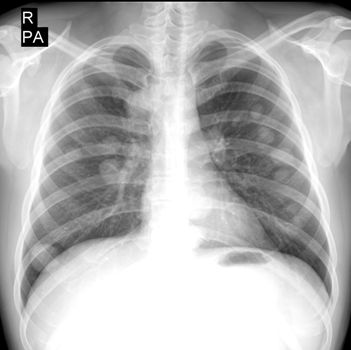

"Пушечное ядро" - метастазы в легкие злокачественного образования

Проведена обзорная рентгенография органов грудной клетки, которая определила классическую картину "пушечного ядра" - метастазов в легкие семиномы яичка.

Множественные узелки практически одинакового размера, от 1 см до 3 см, разбросанные по обоим легким, указывающие на их одновременный рост.